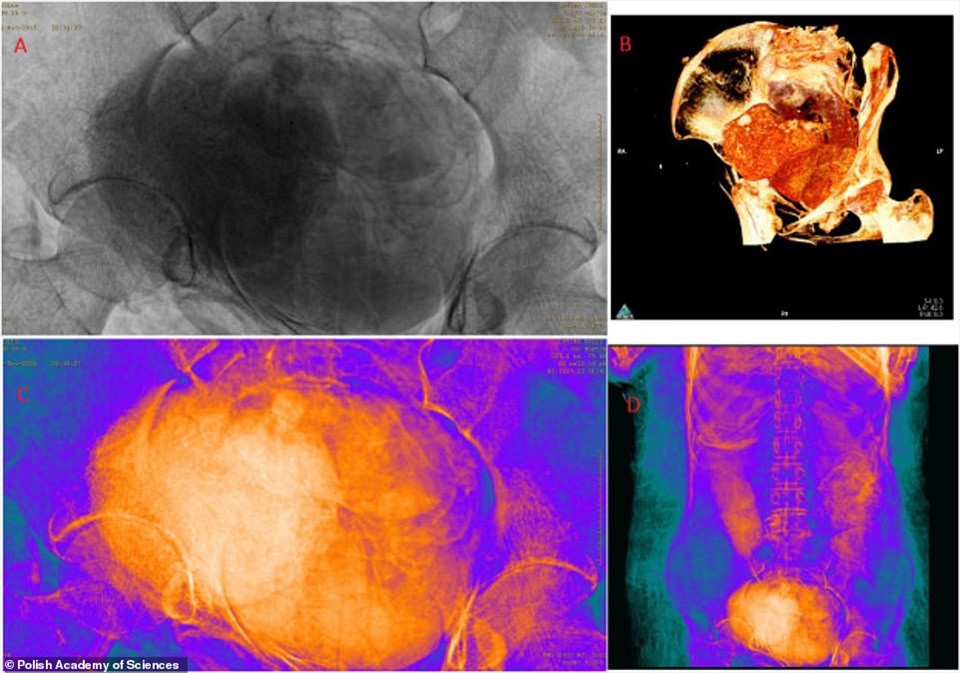

Theo các chuyên gia, xác ướp thuộc về một phụ nữ qua đời khi khoảng 20 - 30 tuổi. Tử cung của người này có một bào thai khoảng 6,5 - 7,5 tháng tuổi.

Đây là lần đầu tiên các chuyên gia tìm thấy xác ướp mang thai. Vì vậy, họ chưa thể lý giải được vì sao thai nghi được giữ trong tử cung của người phụ nữ thay vì ướp xác riêng. Bởi lẽ, thông thường, khi ướp xác, người Ai Cập thời cổ đại thường loại bỏ tim, phổi, gan và ruột cùng dạ dày trong cơ thể và đem ướp xác riêng. Thai nhi cũng như vậy.

Thông qua một số kiểm tra, các chuyên gia xác định niên đại của xác ướp mang thai này khoảng 2.000 năm tuổi. Sau khi qua đời, người phụ nữ được ướp xác. Bên ngoài xác ướp được bọc bằng vải chất lượng cao cùng loạt bùa hộ mệnh tượng trưng cho "Bốn người con của Horus". Điều này cho thấy người phụ nữ đó có địa vị quan trọng ở Thebes hơn 2.000 năm trước.